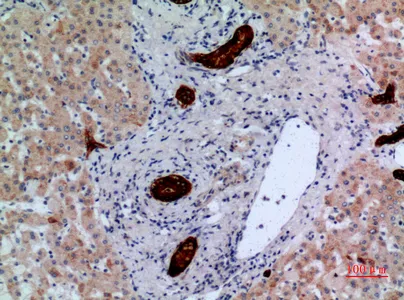

AAT Rabbit Polyclonal Antibody

Cat: APRab06383

Size1:50μl Price1:$118

Size2:100μl Price2:$220

Size3:500μl Price3:$980

Size2:100μl Price2:$220

Size3:500μl Price3:$980